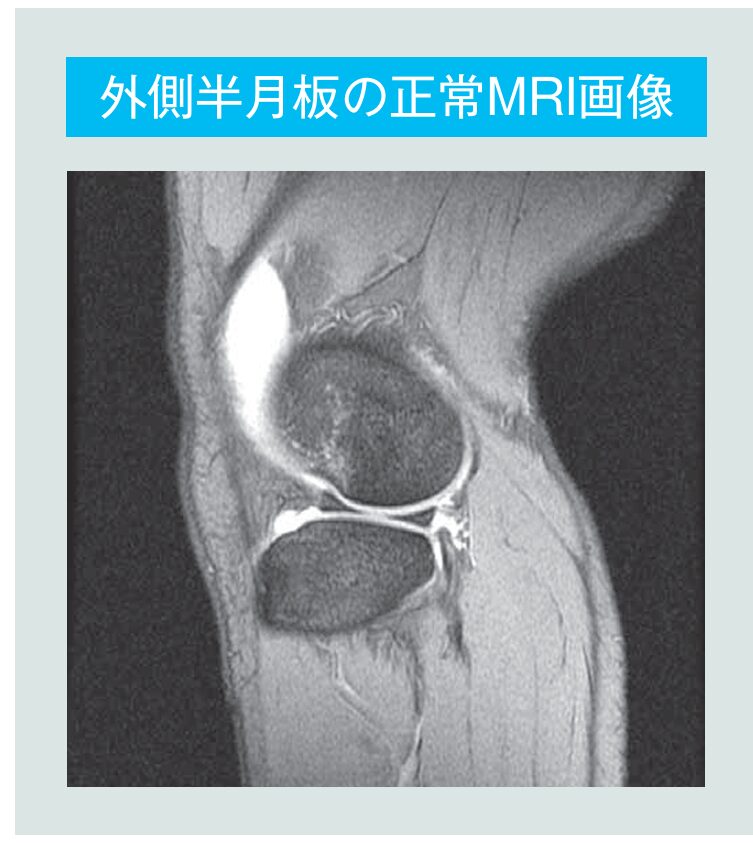

しかしながら現状として、今でも半月板損傷➡切除手術の流れは多いという。「温存する」世界の流れに逆らうようだが、温存するための手術には高い技術と豊富な経験が必要なため、現在も切除手術といった治療法を取る医療機関が少なくない。さらに鬼木院長は大きな課題として「MRI画像ありきの診断」を挙げる。日本は人口100万人あたりのMRI台数が約60台と世界1位(図5)。2位のギリシャの約40台と比べても特出して多く、いわば「気軽にMRIを撮りやすい環境」が整っている。多くの医療施設がMRIを持っているがために、膝の痛みを訴える患者をMRI撮影➡半月板に「傷」を発見➡即手術となるケースが少なからず見られるという。加えて、MRI画像を読み取る専門的知識の不足も鬼木院長は指摘する。「MRIの画像で見ると、正常な半月板と傷ついた半月板の違いや加齢のための変性と損傷の区別は非常に困難です。

膝を専門で見ている医師であっても難しいことさえあります。その結果、切除しなくてもいい損傷であっても切除手術となっている患者が少なからずいます」。加齢によって生じた変性にもかかわらず傷(=半月板損傷)と診断を受け、切除手術を受けた患者が「膝の痛みが取れない」と同院を訪れることもあるという。「結局、膝の痛みは半月板が原因でなかったケースもあります」。半月板損傷をMRI画像で見た場合の正しい診断率は、専門家で85%前後。日頃膝の疾患を診ることが少ない医療機関の場合はさらに正診率は下がると予想される。「5人に1、2人は、傷と思われて切除手術となってしまっているのが大問題なんです」。鬼木院長は力説する。